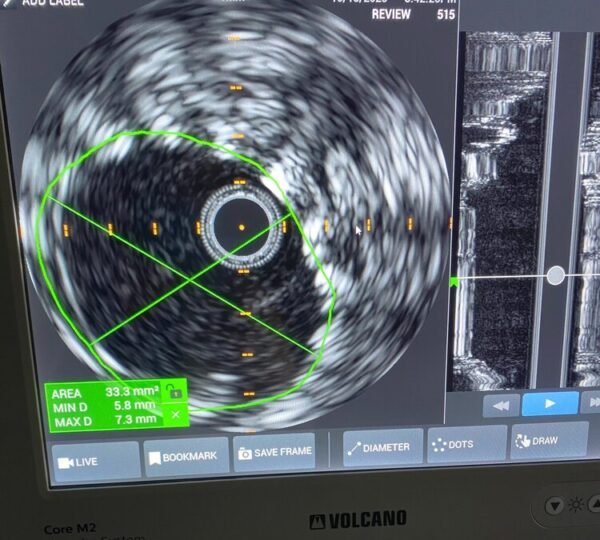

When it comes to arterial disease treatment at Symmetry Vascular Center in Stuart, Florida, our dedicated team of doctors is at the forefront of providing timely and effective care. We understand the importance of early evaluation and intervention for peripheral arterial disease (PAD). Our comprehensive treatment options include procedures carried out in our state-of-the-art in-office angiography suite, designed to minimize co-pays and inconvenience compared to traditional hospital surgeries. For more complex cases, our highly qualified team is credentialed at renowned institutions like Cleveland Clinic Martin Health and St. Lucie Medical Center, ensuring that our patients receive the best care possible. Your vascular health is our priority, and we are committed to delivering peace of mind through expert care and innovative treatments.